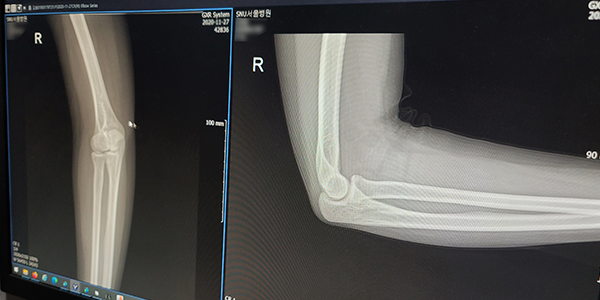

Treatment until the last pain테니스·골프 엘보란 팔꿈치 통증을 유발하는 가장 흔한 퇴행성 질환으로 팔꿈치 근육이 시작되는 부위에 동통이나 압통이 느껴지는 증후군입니다. 팔꿈치 바깥쪽이 아프면 ‘테니스 엘보’, 팔꿈치 안쪽이 아프면 ‘골프엘보’라고 합니다.

X-Ray, 초음파, MRI 등 검사

X선을 이용하여 조영제가 기구 등을 사용하지 않고 인체를 촬영하는 것입니다. 방사선을 인체에 투과하여 나타나는 음영의 차이를 이용해 진단하는 검사로 뼈를 진단할 수 있습니다.